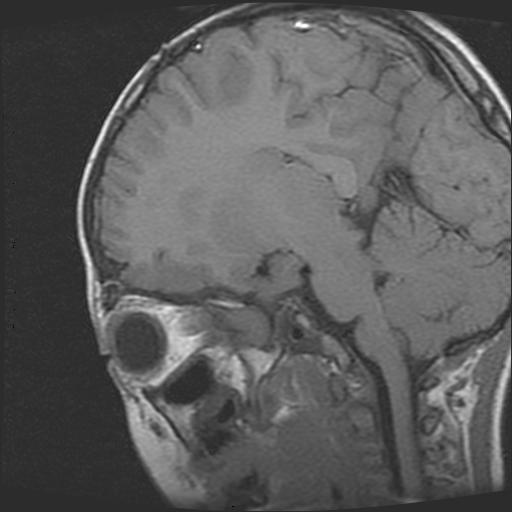

6岁小儿,左侧视神经瘤术后。现左侧视力减退。